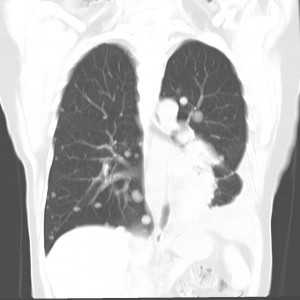

Слева - рак почки с метастазами в легкие, прогноз в данном случае неблагоприятный ввиду метастатического плеврита и дыхательной недостаточности. Определяются очаги с обеих сторон. Справа - мелко- и среднеочаговая диссеминация при раке печени.

Множественные гематогенные вторичные узлы при раке почки, компьютерная томография (КТ).